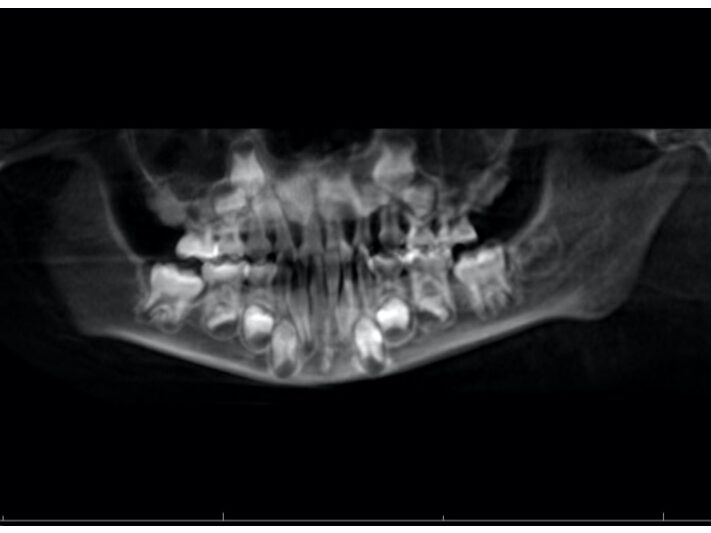

A

B

ご兄弟で同じ歳の時期に撮影したものです。歯の形やある程度のアーチはやはり似ていますが、下顎前歯の傾斜や生え変わりなどの違いがあります。

兄弟姉妹でも、歯の大きさや生える角度、あごの骨格には違いがあります。

たとえば、一方が「出っ歯」で、もう一方が「受け口」という場合もあり、治療法や始める時期が異なるのは当然です。